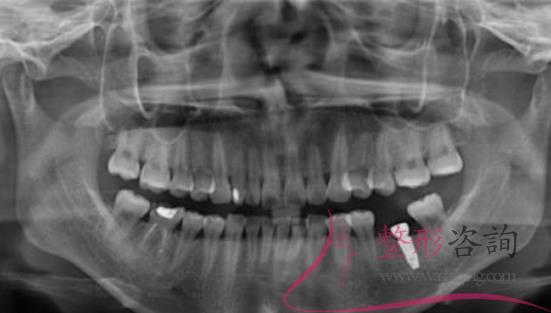

聽(tīng)說(shuō)深圳種植牙齒比較好,爸爸的牙齒少了很多,如果不及時(shí)的去補(bǔ)充就會(huì)影響到周?chē)难例X,假牙不方便,而且也不能咬硬的東西,所以決定去深圳種植牙齒,聽(tīng)說(shuō)種植牙齒和真的牙齒一樣,隨便用,不會(huì)對(duì)人們?cè)斐捎绊?,?jīng)過(guò)仔細(xì)的了解到深圳種植牙的價(jià)格后,帶爸爸去正夫口腔醫(yī)院做了種植牙。

通過(guò)各種了解后,最后決定帶著爸爸來(lái)到了深圳正夫口腔醫(yī)院種植牙齒,來(lái)到醫(yī)院后,醫(yī)生仔細(xì)檢查了爸爸的身體,經(jīng)過(guò)仔細(xì)的確認(rèn)爸爸的身體沒(méi)有任何的異常情況,醫(yī)生才選擇了手術(shù),手術(shù)前爸爸有一些緊張,但是醫(yī)生耐心的溝通,徹底的消除了爸爸的緊張感,就著手準(zhǔn)備手術(shù)了,差不多經(jīng)過(guò)3個(gè)左右的時(shí)間,手術(shù)結(jié)束了。

爸爸說(shuō),這次手術(shù)并沒(méi)有疼痛感出現(xiàn),整個(gè)手術(shù)都非常的輕松,剛種植完牙齒后會(huì)有一些不適應(yīng),可能是麻藥的緣故,醫(yī)生說(shuō)麻藥藥效散去后會(huì)有一些疼痛感出現(xiàn),爸爸說(shuō)是有一些疼痛感,但是并不是非常明顯,這種疼痛也是可以忍受的。

種植牙齒半年后

距離種植牙齒已經(jīng)有半年左右的時(shí)間了,爸爸說(shuō)已經(jīng)適應(yīng)了這種情況,一切都非常的好,牙齒也可以咬各種東西,現(xiàn)在爸爸再也不會(huì)擔(dān)心這種食物不能吃,那種食物不能吃了,全部都可以吃了,硬的食物,酸的食物,甜的食物都不會(huì)再引起牙痛了,這次種植牙齒真的非常滿意。